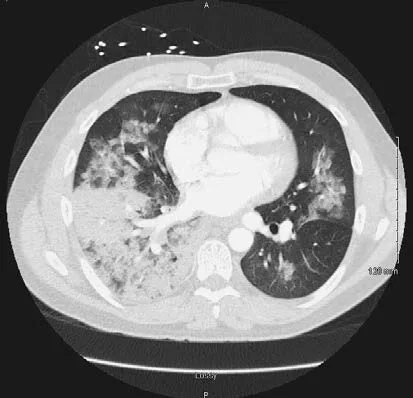

住院治疗2天后患者呼吸困难症状进一步加重,需10L/min面罩吸氧来改善呼吸困难症状。胸部CT显示:双侧磨玻璃影,双侧少量胸腔积液,右肺门隆突下淋巴结肿大(图2)。痰革兰氏染色显示:革兰阴性杆菌。但痰培养显示为呼吸道正常菌群(48小时)。

图2. 患者出现临床症状1天后的胸部CT示:双侧磨玻璃影,部分存在小叶间隔和小叶内线增厚。